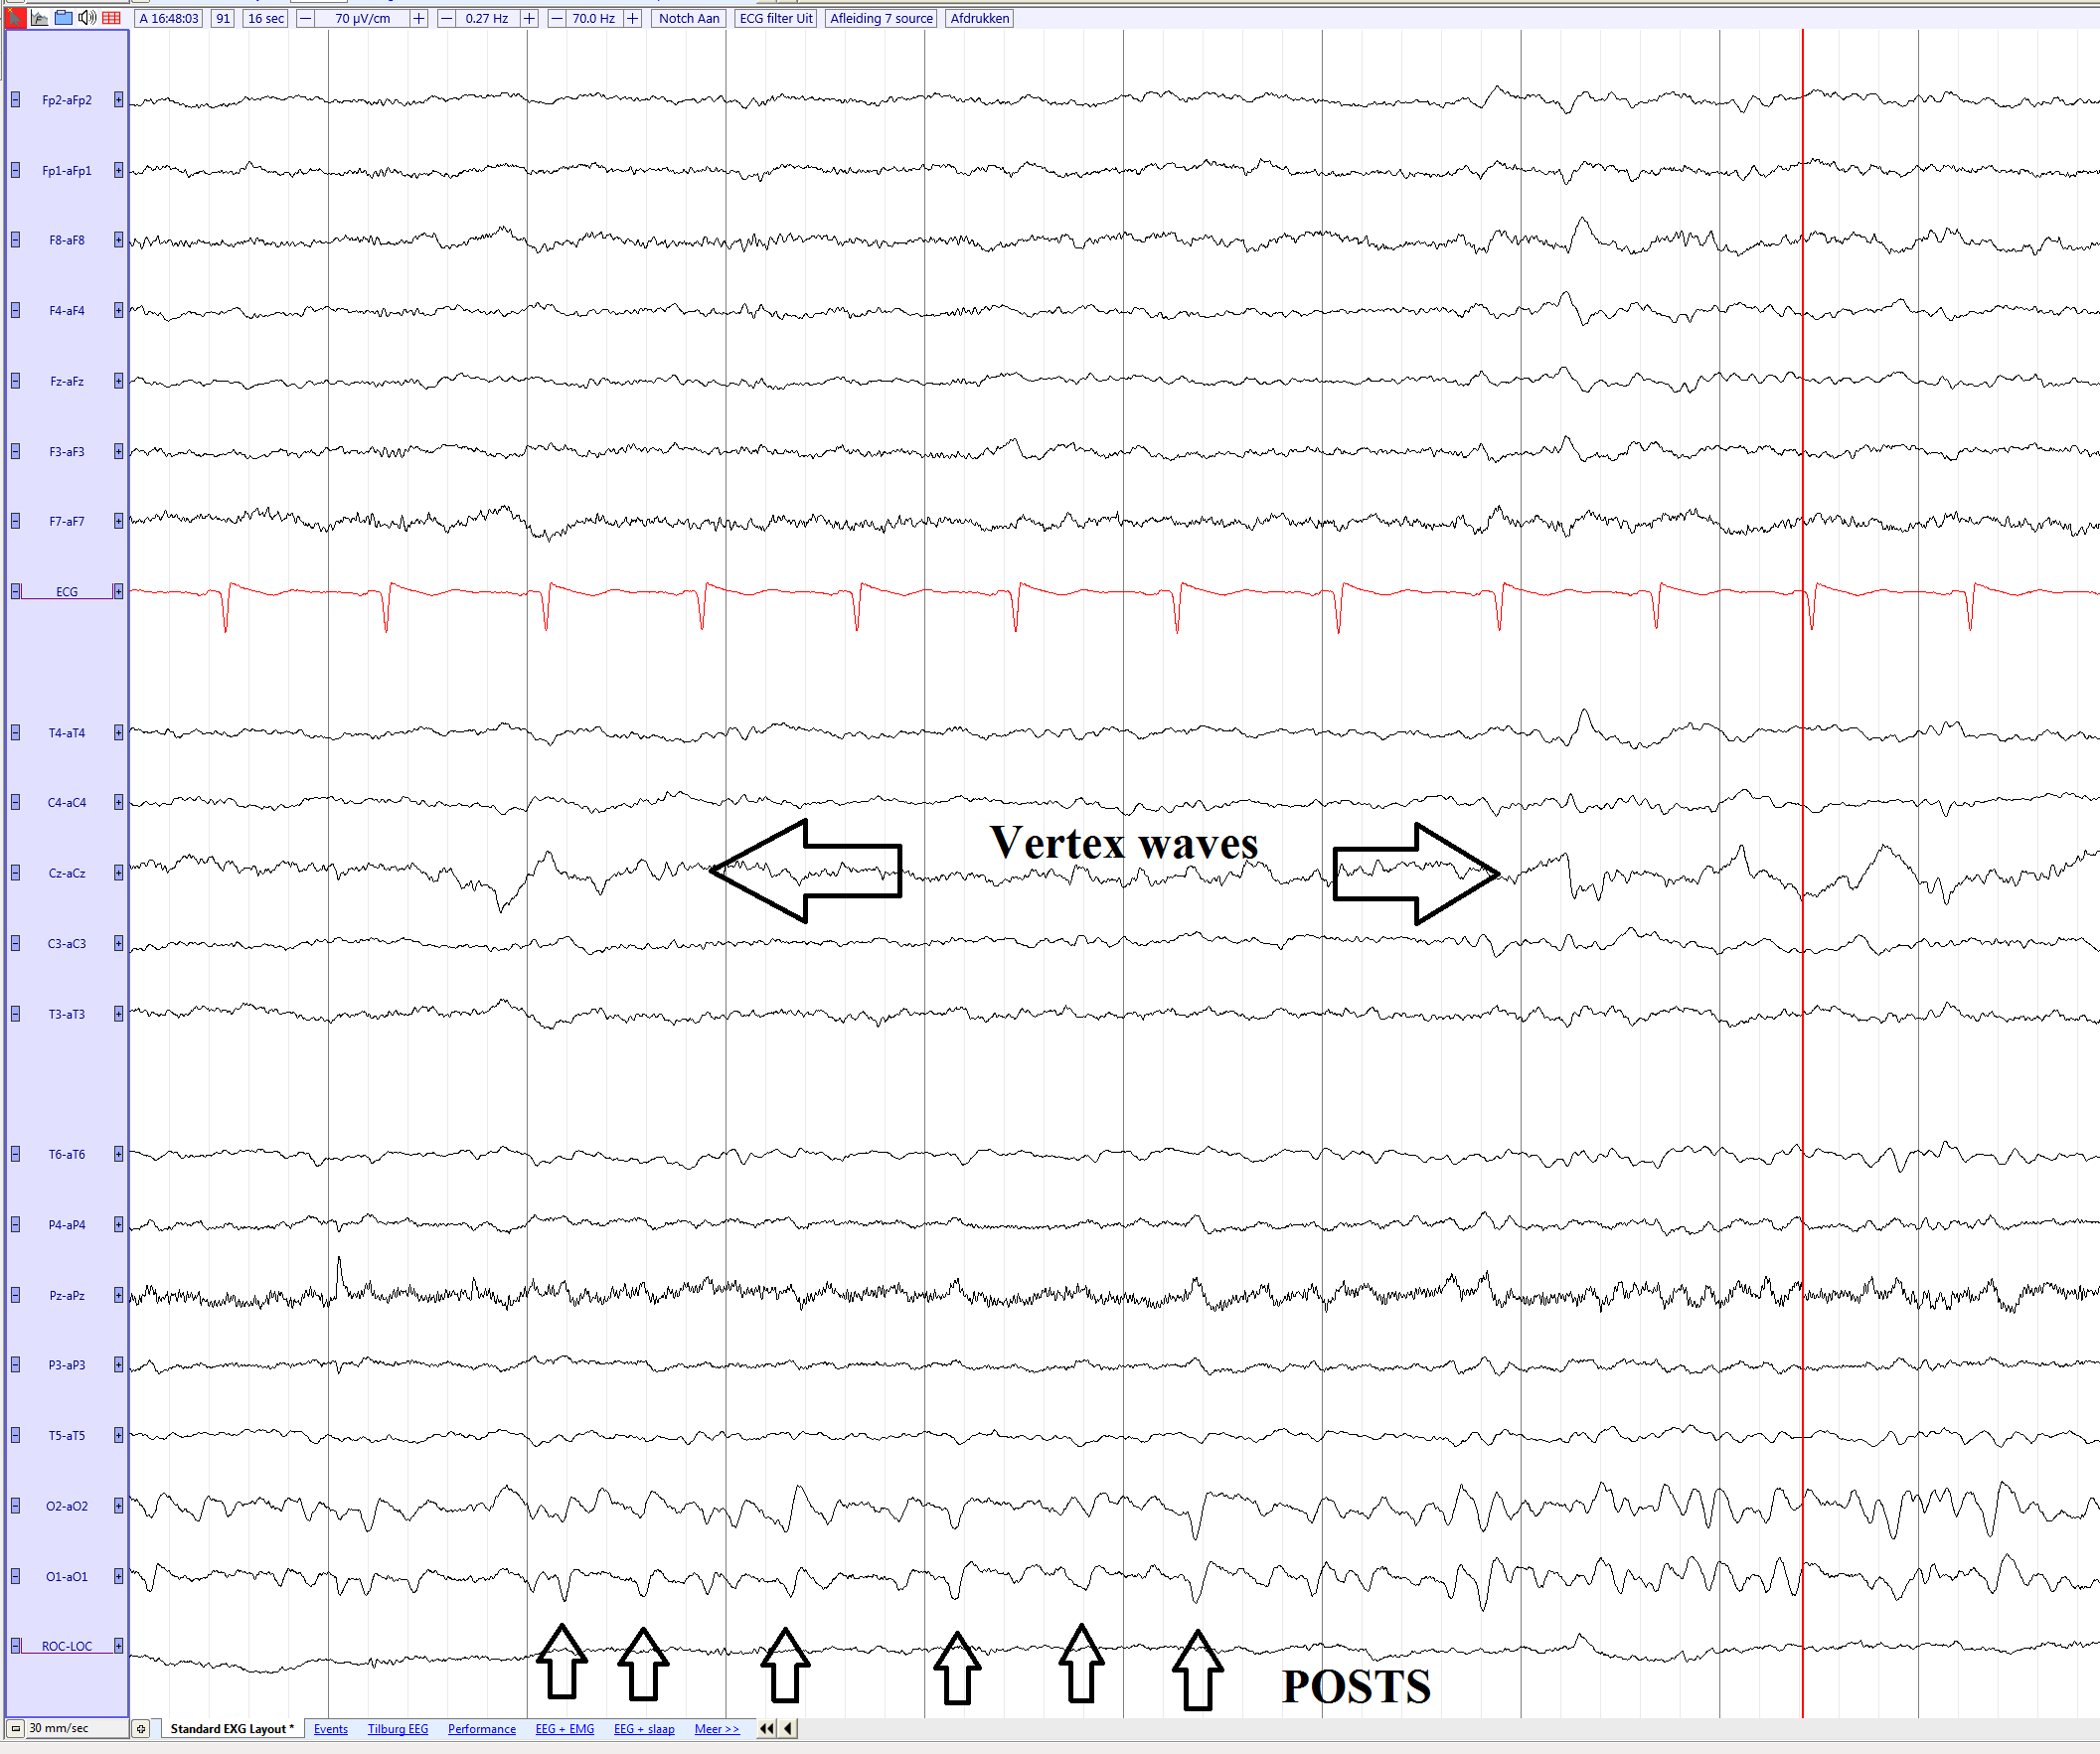

POSTS and vertexwaves in a young female adult in non REM 1 sleep

| current | 16:25, 30 March 2017 | 2,113 × 1,765 (257 KB) | EEGpedia (Talk | contribs) | POSTS and vertexwaves in a young female adult in non REM 1 sleep |